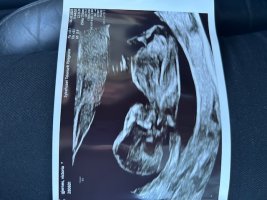

Fikk ikke lagt ved bilde på forrigeJordmor ville ikke si, så vi vet ikke enda..

Synes det ser ut som en liten gutt13+2 og alt bra

Tror ikke det er mulig å se nub her?